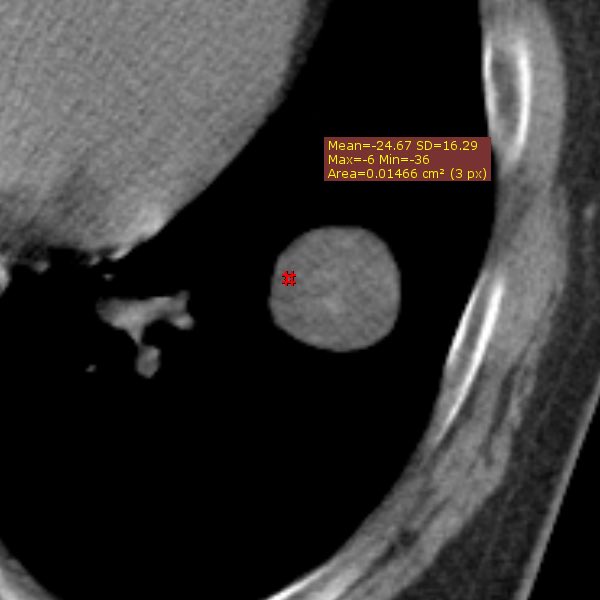

CT上吸収域が低い末梢の境界明瞭な分葉状の辺縁を有する結節として認められ

特徴としてはポップコーン様の石灰化が言われていますが、出現頻度は低く

22%程度と言われ、吸収域の低さは -33HU を閾値として採用した場合の

精度、感度、特異度はそれぞれ、95%, 100%, 96% と言われ

過誤腫の検出能力が構造する可能性が言われています。

Hochhegger B, et al. J Thorac Imaging. 2016 Jan;31(1):11-4

当院の症例では初診時はCT値の低そうなところを測定しても−24HU程度で

その報告の閾値では診断が困難でした。画像的には淡い点状石灰化も含まれており

CT値も比較的低かったので、読影者は過誤腫と読影しています。

大きくなってからは、CT値が-30HUを下回る低吸収域を示す部分が

まだら状に混在し、ポップコーン様の粗大な石灰化も明瞭に認められ

診断は容易となっています。かなり増大したという点が手術をした理由です。